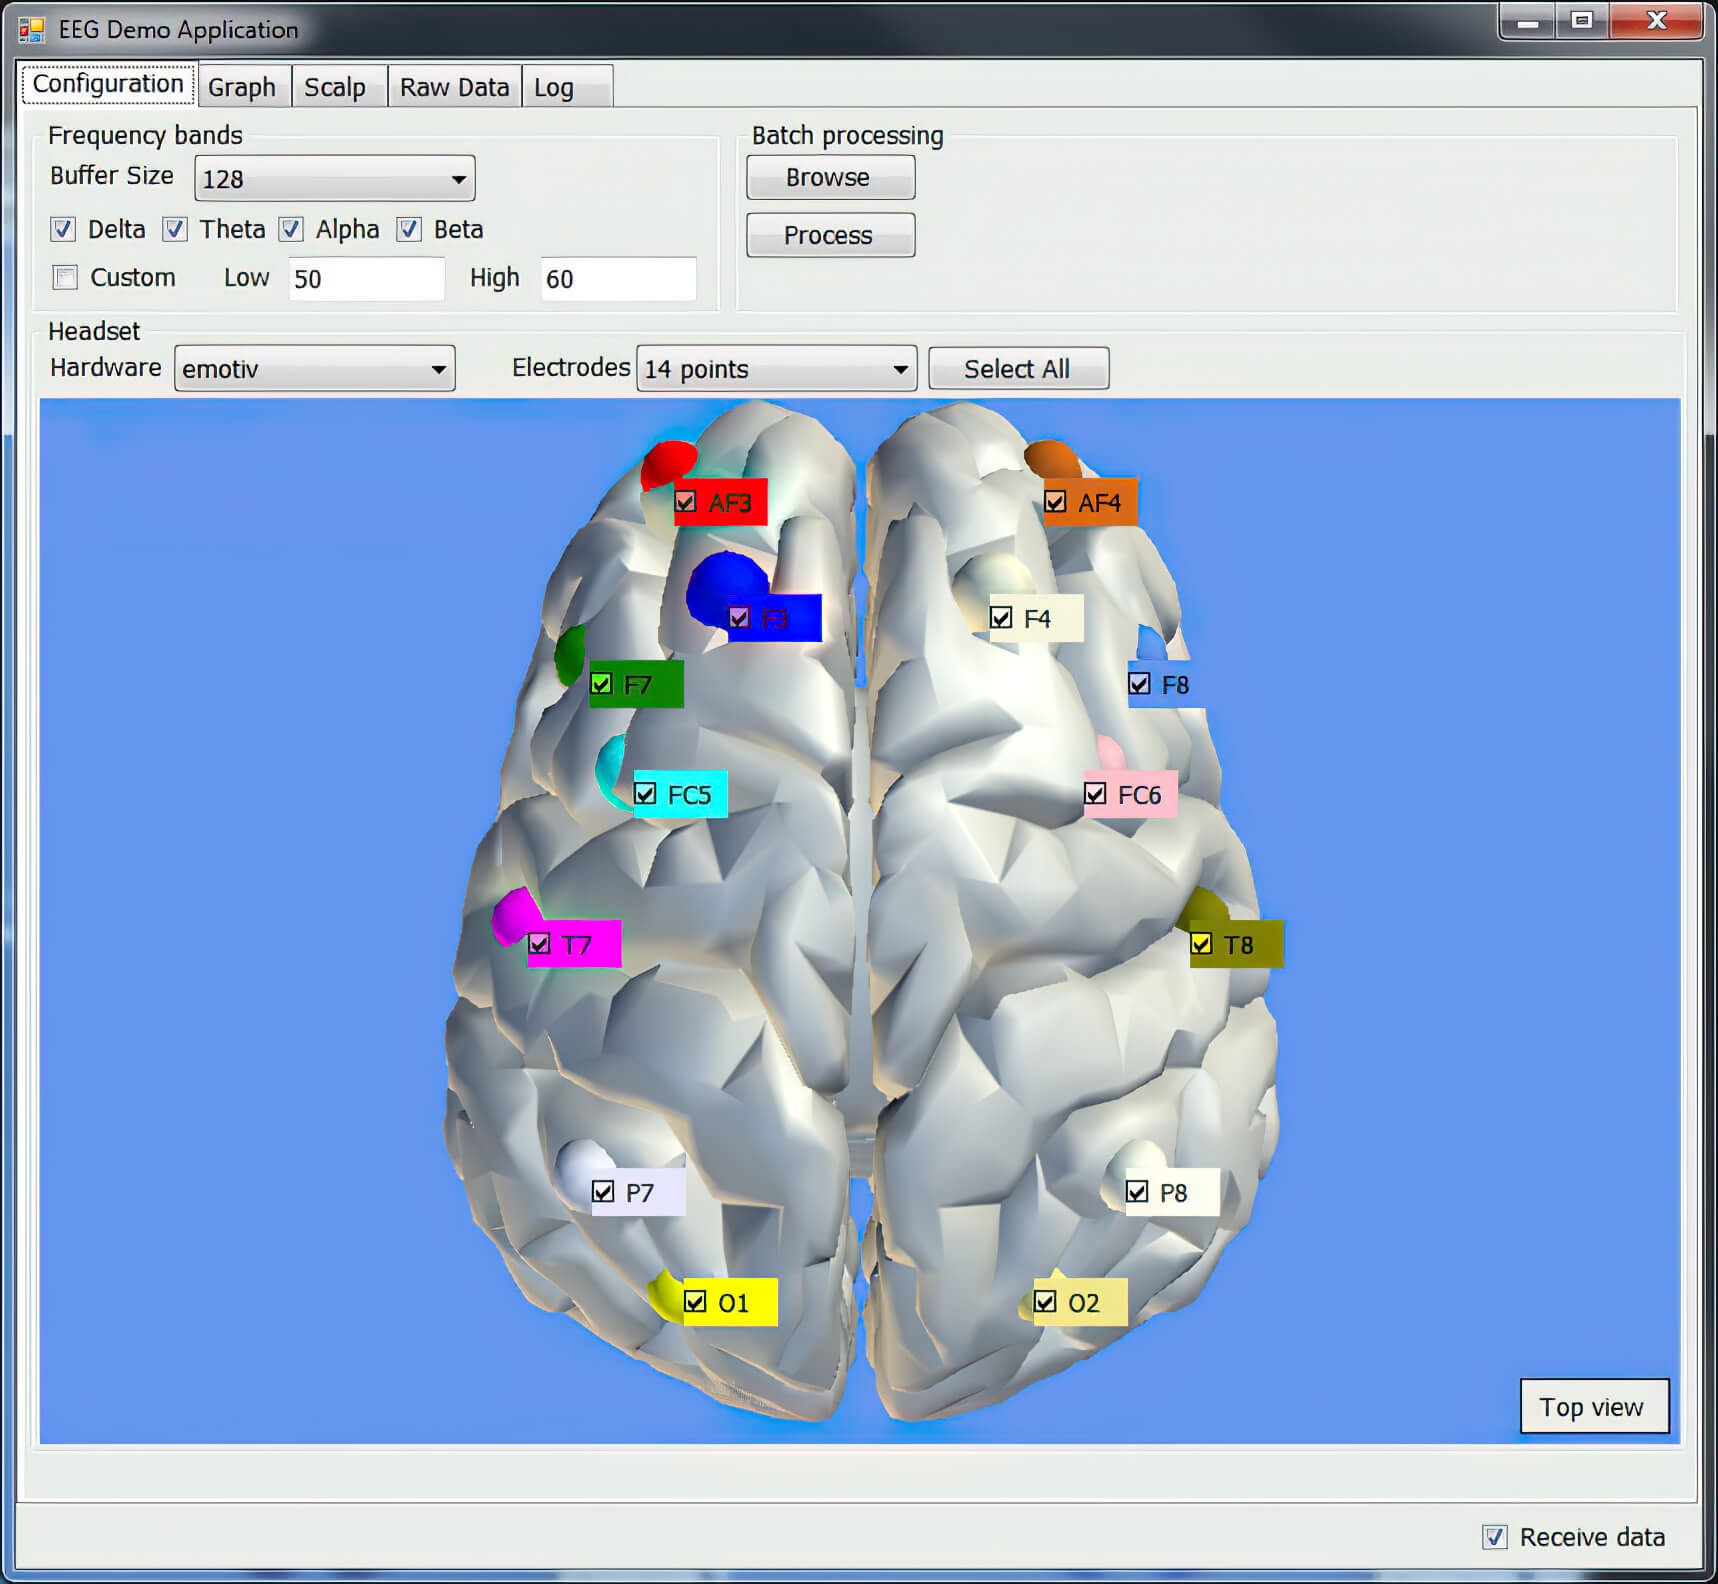

Конфигурация датчиков

Проект по анализу внимательности на основе сигналов энцефалограммы. Приложение принимает сигналы от датчиков, закрепленных в определенных точках на голове пациента.

Проводит частотный анализ, анализирует гармоники (альфа, бета, тета, дельта-ритмы) и визуально отображает их на 3D модели головного мозга. Данные могут приходить как прямо с устройства в реальном времени, так и быть загружены из проведенных ранее сеансов.